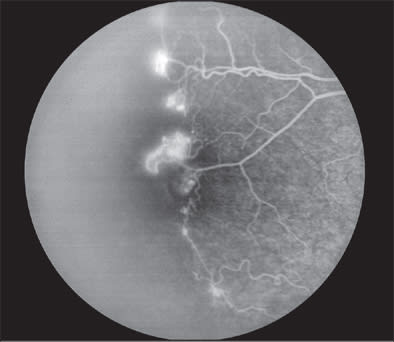

As in PDR, patients with sickle-cell hemoglobinopathy can develop peripheral neovascularization when vascular occlusions induce retinal ischemia. Hemoglobin is the main oxygen-transport protein within the erythrocyte. The hemoglobin protein in patients with sickle-cell anemia is altered by a single amino acid substitution of valine for glutamine, causing polymerization of the deoxygenated hemoglobin and sickling of the erythrocyte. It is currently believed that the rigid, elongated, and sickle-shaped erythrocyte causes mechanical microvascular occlusions, resulting in retinal ischemia. Furthermore, the sickled erythrocytes irritate the endothelial cells, stimulating a cascade of inflammatory events leading to vascular stasis and prearteriolar capillary occlusion. Neovascularization occurs at the border of ischemic and nonischemic tissue in the peripheral retina (Figure 2). The neovascularization is classically described as sea-fan neovascularization, but this is not pathognomonic for sickle-cell hemoglobinopathy and can occur in other retinopathies.14

Figure 2. In this picture, the left side is more peripheral and more anterior; the right is more posterior. On the left side, the peripheral retina is completely nonperfused. The right side shows a partially perfused retina. The brighter areas are the junction where the neovascularization is leaking.